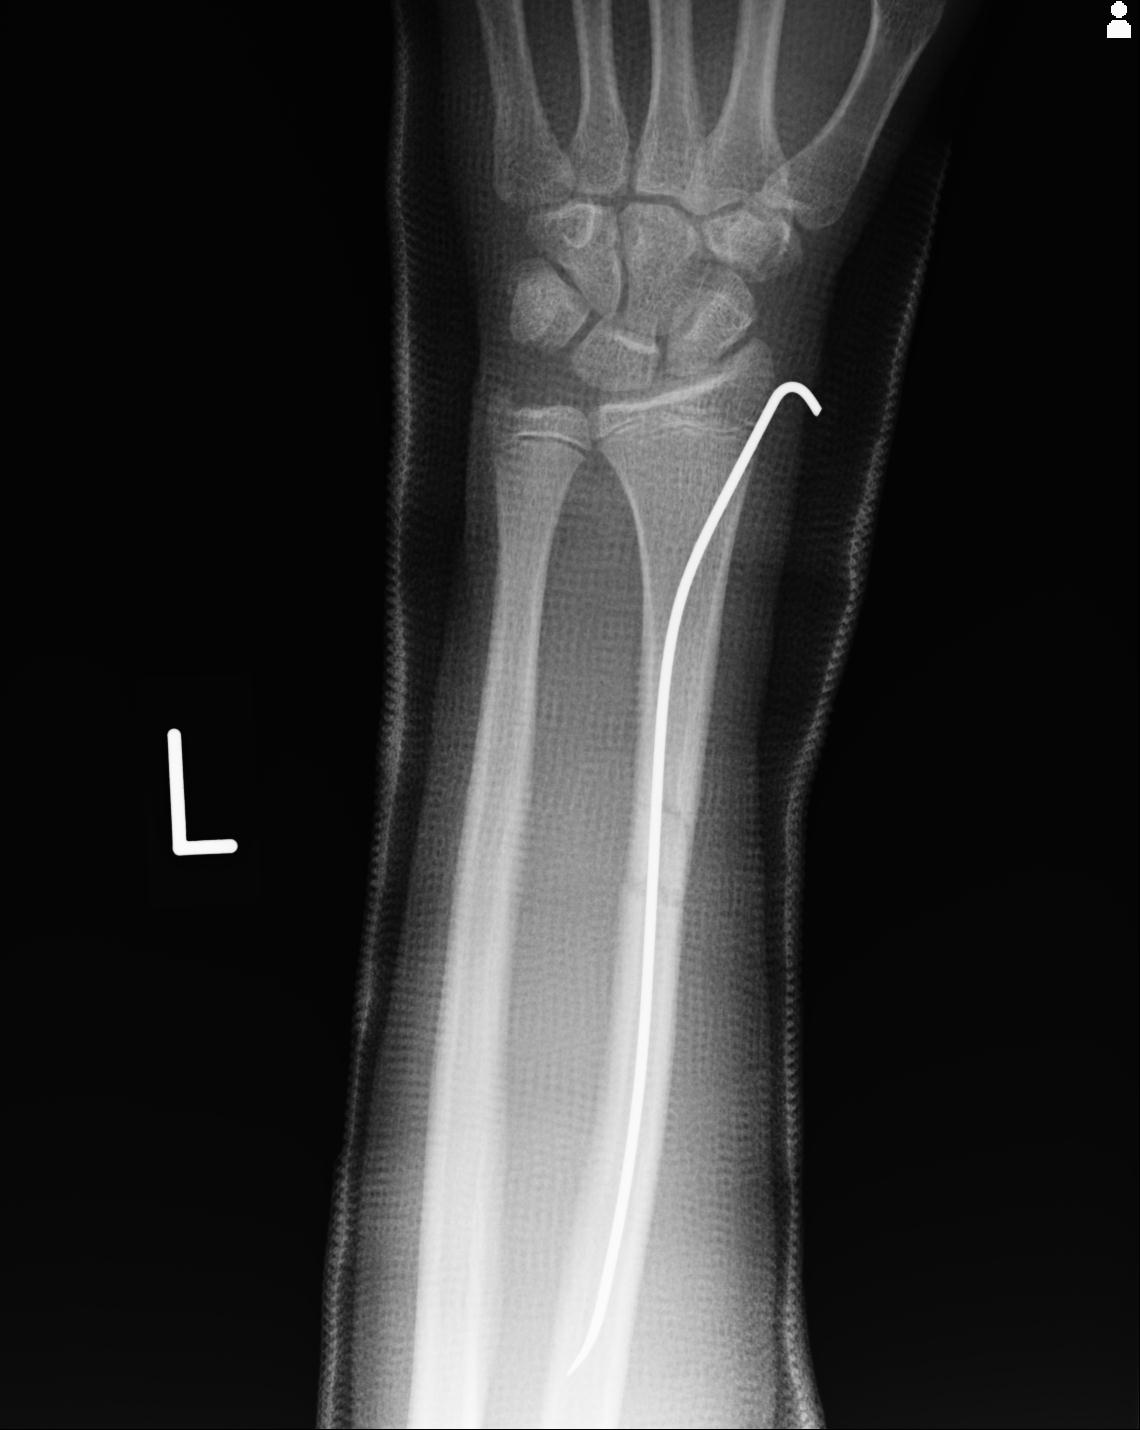

110211 1/6 1/8 左前腕 4R 15歳男性 橈骨骨幹部骨折